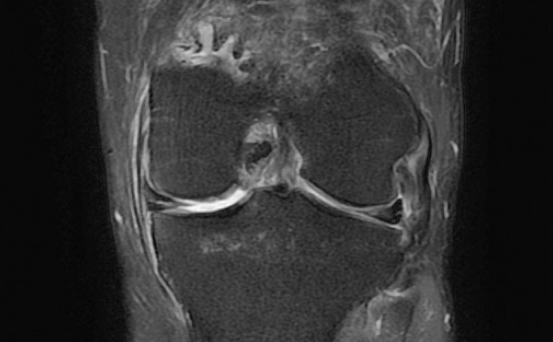

일부 환자의 경우 운동량 조절과 물리치료 등 보존적 치료로도 경과를 지켜볼 수 있지만, 혈류가 거의 없는 중심부 손상의 경우 봉합수술이나 부분 절제술 등 수술적 접근이 필요할 수도 있습니다. 즉, MRI 등 영상 검사를 통해 손상 범위와 유형을 정확히 파악하는 것이 중요합니다.

단순 근육통은 보통 휴식 후 통증이 완화되지만, 연골판 손상의 경우 통증이 지속되거나 무릎이 뻣뻣하고, 구부리거나 펼 때 ‘딱’ 소리가 나며 걸리는 느낌이 동반됩니다. 또한 부기나 잠김(locking) 증상이 있다면 단순 근육통이 아니라 연골 손상 가능성이 높습니다. 이럴 때는 반드시 정형외과 진단과 MRI 검사를 통해 정확한 확인이 필요합니다.

모든 연골판 손상이 수술로 이어지는 것은 아닙니다. 손상 부위가 혈류가 있는 외측이라면 약물치료, 물리치료, 냉찜질, 생활습관 교정 등 보존적 치료로 회복될 수 있습니다. 그러나 손상 범위가 크거나 혈류 공급이 어려운 부위라면 관절내시경 시술 등 수술적 치료가 필요할 수 있습니다. 정확한 판단을 위해 MRI 검사로 손상 정도를 파악하는 것이 중요합니다.